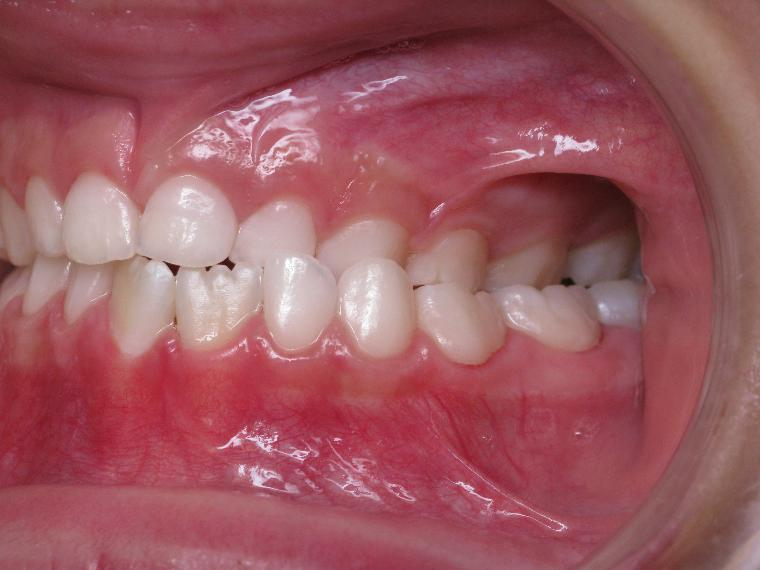

9. inversé gauche 6 ans

inversion des dents posterieur cote gauche

sectionnel multibagues pendant 25 mois

surveillance évolution de la dentition pendant 4 ans